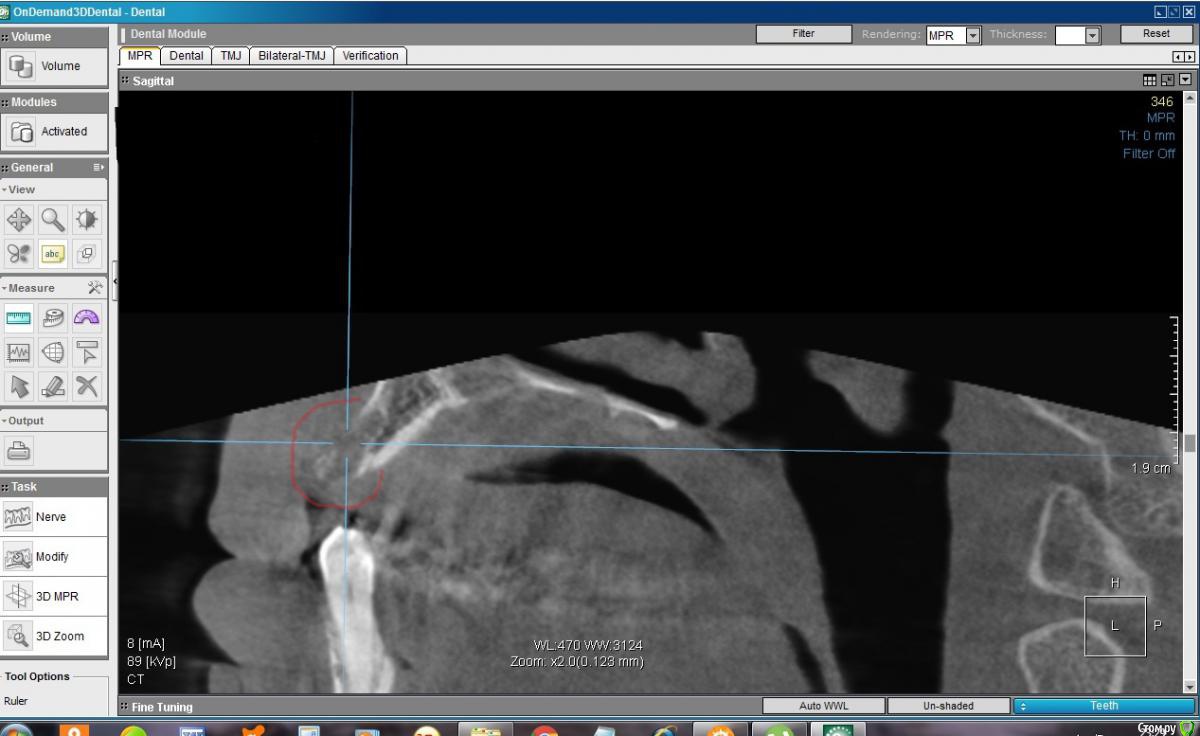

konst2009 Опубликовано 26 августа, 2019 Поделиться Опубликовано 26 августа, 2019 Здравствуйте.Два с половиной месяца назад удалил верхние передние 4 зуба. Вчера сделал KT. В сагиттальной проекции на месте лунок удаленных зубов вместо ожидаемой костной ткани как будто пустота, где-то даже губная пластина не просматривается. Срезы между лунками: Такое разве пригодно для имплантации? Что делать, ждать? Ссылка на комментарий

konst2009 Опубликовано 27 августа, 2019 Автор Поделиться Опубликовано 27 августа, 2019 Здравствуйте! После удаления зуба,объём костной ткани неминуемо уменьшается,чем больше времени после удаления-тем меньше костной ткани останется Понятно, но в лунках, если я правильно понимаю, после удаления сначала образовывается кровяной сгусток, а потом костная ткань, а ее почему-то на КТ не видно, как будто там пустота, как это можно объяснить? Ссылка на комментарий

колесников Опубликовано 27 августа, 2019 Поделиться Опубликовано 27 августа, 2019 Слабоминерализованая,потому не контрастируется Ссылка на комментарий